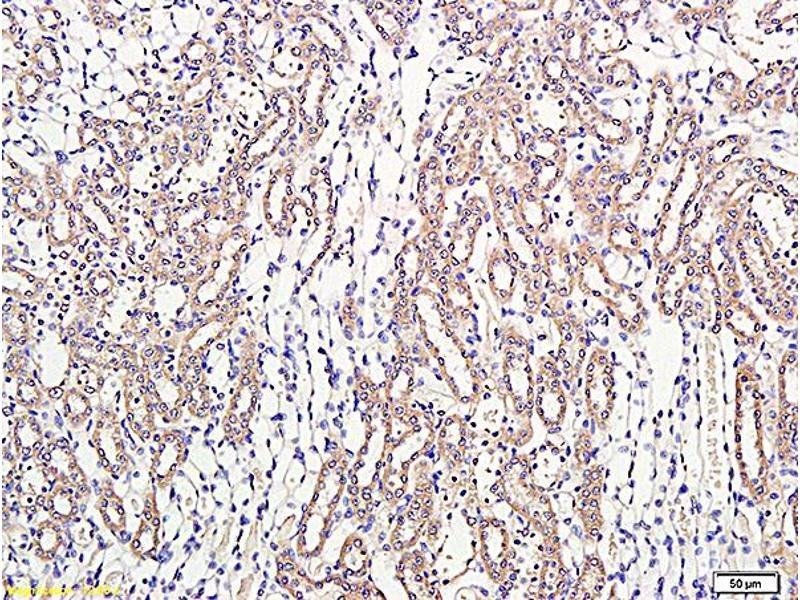

THBD 适用: 人, 小鼠, 大鼠, 犬, Cow WB, IHC (p), IF (p) 宿主: 兔 Polyclonal unconjugated

产品编号 ABIN669636